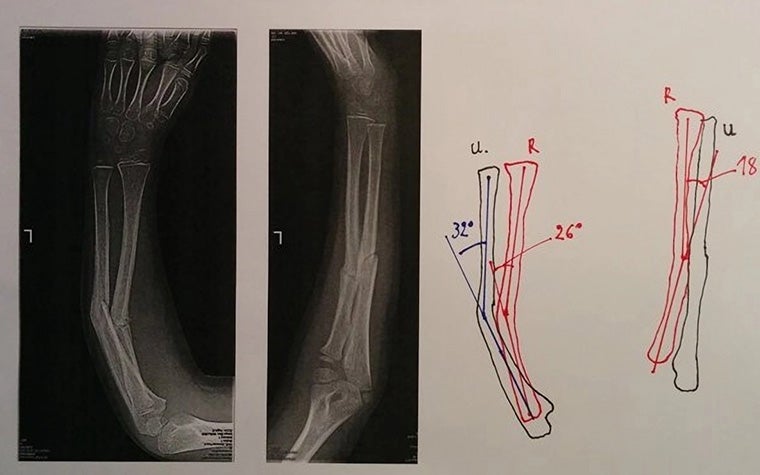

Dr. Verstreken has incorporated 3D technology into his practice for 14 or so years now, and many of his cases have benefited from 3D planning and printing. One that stands out is a seven-year-old child who had broken their arm in three places. Traditionally, just a cast would be enough to treat this type of break. However, for this patient, the cast mended the bones at an incorrect angle.

Typically, surgeons actually planned for this operation using pen and paper. "Maybe even today, this is the way surgeries are planned," explains Dr. Verstreken. "Taking a piece of paper, drawing the outlines, and looking at the correction of the angles. Then you go into the operating room and try to do the best you can to restore the anatomy. But it's not as easy as that."

3D offers so much more than that. Drawn diagrams only provided a way to address angulation. By planning in 3D, the surgeon can manage malrotation as well as the lengthening and shortening of the bone in his preprocedural plan. "We really want to make sure that we're restoring the anatomy as precisely as possible," says Dr. Verstreken. "And that's where 3D technology can be extremely helpful."

The process began by compiling CT scans of both arms into a 3D visualization. From there, Dr. Verstreken compared the mirrored 3D image of the healthy forearm with the abnormal forearm. And next came planning. He conducted a virtual surgery with the 3D visualizations, deciding where to lengthen and shorten bones, how exactly he should cut the bone, and where to insert the graft.